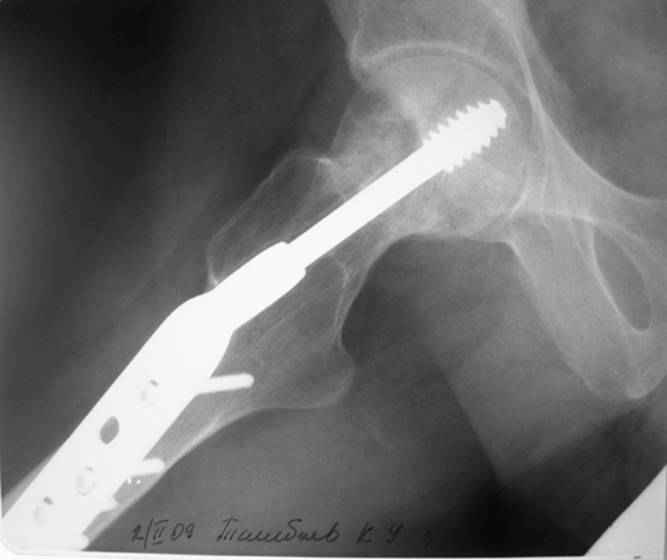

Больной Т. 1966 г.р.Травма 28.06.2007. Прооперирован в г. Бишкек, Оп: Остеосинтез правого бедра системой DHS. В последующем беспокоили периодические боли в правом тазобедренном суставе с иррадиацией в коленный сустав в область передней поверхности правого бедра. Лечился амбулаторно с незначительным эффектом. В 07.04.2008 по 08.05.2008 года лечился в госпитале ГУВД и СО в стационаре с Срастающийся перелом шейки правого бедра в условиях фиксации системой DHS – боли уменьшились.Боли обострились 03.02.2009 внезапно, госпитализирован. Результат - Псевдоартроз шейки правого бедра (имеются косвенные признаки разрушения спонгиозной части головки бедра)Планируется - Работает милиционером. Имеющийся опыт протезирования у данной категории во всех случаях в ближайшее время заканчивался дисквалификацией. Работоспособный возраст (43 года).Наиболее приемлемым и реальным методом лечения предполагается: Удаление конструкций из бедра. Заполнение полости от винта монолитным аутотрансплантатом из крыла (крылев) подвздошной кости. Медиализация большого вертела. Предполагаемый период нетрудоспособности 3-4 мес.

На более раннем снимке репозиция была, мягко говоря, далека от идеальной. Плюс перелом шейки слишком проксимальный для фиксации одном винтом. Неудача тут закономерный исход.

Но в данном случае DHS сыграл как имплант с угловой стабильностью, что привело к прорезыванию импланта в верхнем сегменте головки. Отсутствие трехточечной опоры и длинный имплант увеличивают нестабильность в шейке.